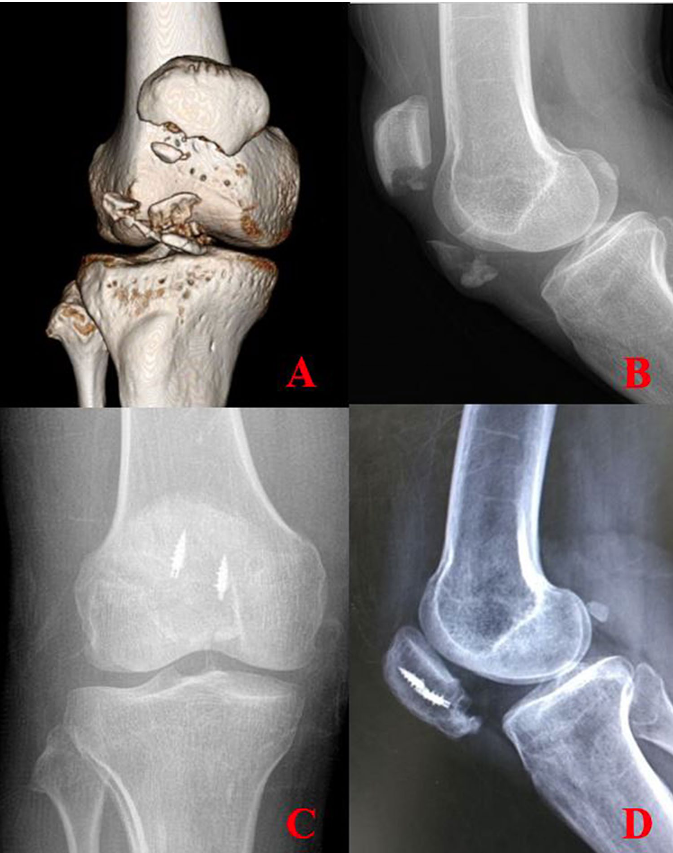

本研究回顾性纳入了2017年3月至2018年12月期间接受缝线桥锚钉固定治疗的22例患者,其中21例为髌骨下极粉碎性骨折,1例为下极骨膜套袖撕脱骨折(图1)。所有患者术后均随访1年以上以评估骨愈合情况,平均随访时间为25±18个月(范围11-74个月)。

图1 使用缝线桥锚钉固定下极骨折块的术前及术后X线片

术后即刻鼓励进行股四头肌等长收缩练习。膝关节支具在完全伸直位佩戴四周,术后4周开始进行关节活动度和股四头肌锻炼。末次随访X线片确认这些粉碎性下极骨折完全愈合(图3)。

所有22例患者均实施了缝线桥锚钉固定。涉及13名男性和9名女性患者。平均年龄为46±20(15-82岁),平均随访期为25±18(11-74)个月。平均BMI为24(20-33)。15例患者为右膝髌骨骨折,7例为左膝(表1)。平均术后4个月,所有患者均达到骨愈合(图3)。但我们取出了2例附加的克氏针张力带钢丝。